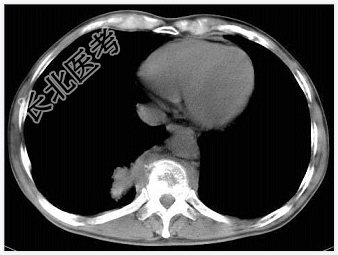

- [材料题] 男,32岁,低热、腰背痛,活动受限。

- 简答题1、结合CT检查,最可能的诊断是?